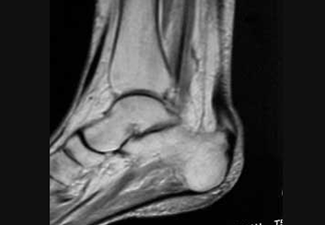

Resonancia magnética nuclear donde se observa el engrosamiento del tendón de aquiles.

Es la degeneración estructural del tendón. Clínicamente se manifiesta con dolor sobre el tendón, con limitación o no a la dorsiflexión, crepitación y edema tipo fusiforme. A pesar que su diagnóstico es fundamentalmente clínico, los estudios complementarios pueden aportar información con respecto a la estructura tendinosa como calcificaciones evidenciables en una radiografía o en una ecografía, engrosamientos y patrones de diferentes intensidades a nivel de la RMN